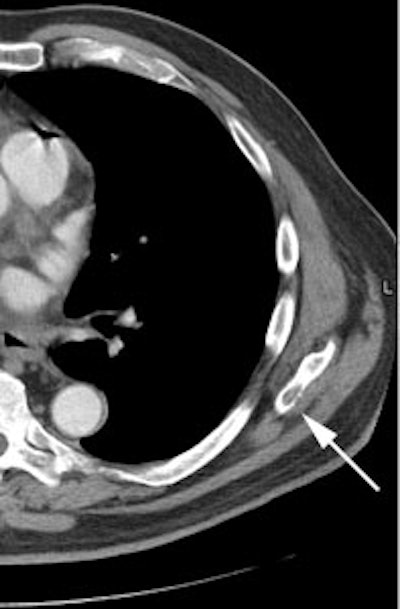

|

Unsuspected bone metastases: The patient shown below had a cavitary left lung non-small cell lung cancer. There was no uptake of tracer within the aortopulmonary window lymph nodes detected on CT to suggest metastases, however, unsuspected bone metastases were found in the left anterior 4th rib (black arrow) and lumbar spine (red arrows- not included in staging lung CT scan). The presence of bone metastases significantly alters patient prognosis and management. PET imaging provides a rapid whole body survey for the detection of unsuspected metastatic disease. |